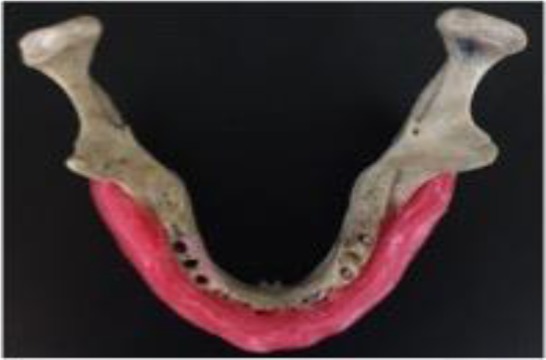

Fig. 1:

The mandibular bone covered by soft base plate wax.

Three parallel holes with 3mm diameter and 8mm height were placed in the mandible. The anterior hole was drilled at the canine site, the middle hole was created at the second premolar site, and the posterior hole was created at the distal root of the first molar site. The distance from the anterior and posterior holes to the middle hole was the same. In order to simulate the beam attenuation effect of soft tissue, the bone surface was covered with layers of soft base plate wax with a total thickness of 15 mm (Fig. 1). Titanium rods were first placed into the holes and the mandible was scanned using the Promax 3D unit (Planmeca, Helsinki, Finland) with different currents (8, 12, and 16 mA) and different voltages (70, 78, and 84 kVp), with 8×8cm field of view and 0.16 mm voxel size. Next, the cobalt-chromium rods were placed into the holes and the same process was repeated (Fig. 2).